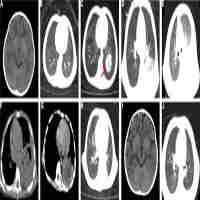

| Abstract | Geotrichum capitatum infection has a very low incidence rate with atypical clinical symptoms, making diagnosis difficult, and it has a poor prognosis. The incidence is even more rare in China. This paper reports the first case of infection caused by G. capitatum during bone marrow suppression after chemotherapy in a Chinese patient with acute lymphoblastic leukemia. In addition, it reports a systematic literature review of diagnosis and treatment. The patient with acute lymphoblastic leukemia was confirmed to be infected with G. capitatum, involving lung, liver and skin, through a blood culture test. Caspofungin, amphotericin B loposome, and a combination therapy of amphotericin B liposome and voriconazole were used in succession for treatment. Despite normal body temperature and a slight improvement of clinical symptoms with the combination therapy treatment, the patient died 40 days after chemotherapy due to heart and lung failure. |